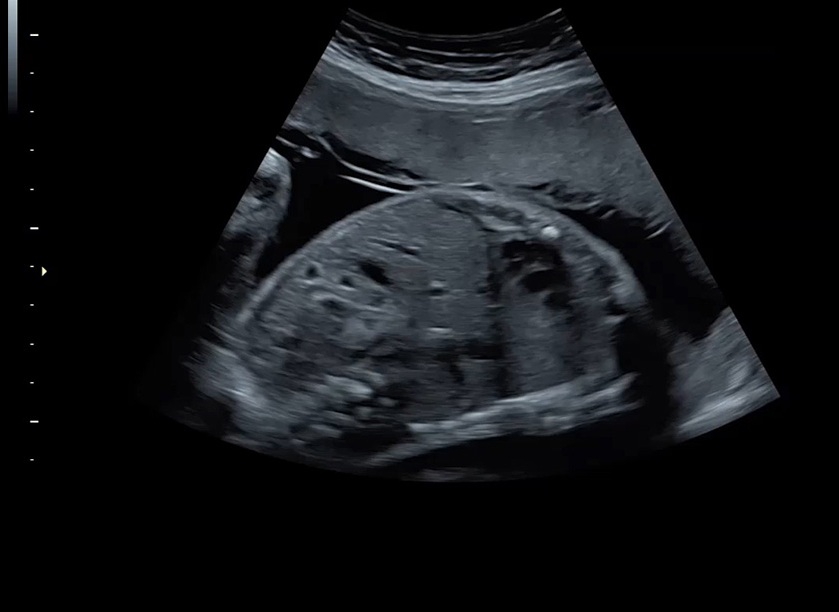

Ультразвуковая платформа Voluson S8 представляет собой оборудование экспертного класса с передовыми возможностями и высоким уровнем автоматизации процессов. Она позволяет проводить сканирование в режимах 2D, 3D и 4D с высоким качеством изображений.

Аппарат Voluson S8 базируется на надежной платформе VCA, которая имеет множество положительных отзывов. Она обладает высококонтрастной технологией объемной реконструкции, обеспечивая качественное воспроизведение изображений. Информация выводится на широкоформатный цветной монитор размером 23 дюйма для убедительной демонстрации плода будущим родителям и облегчения работы врача.

• Высокое качество изображений: Voluson S8 обеспечивает высококачественные изображения, позволяющие детально оценить состояние плода и обнаружить возможные патологии.